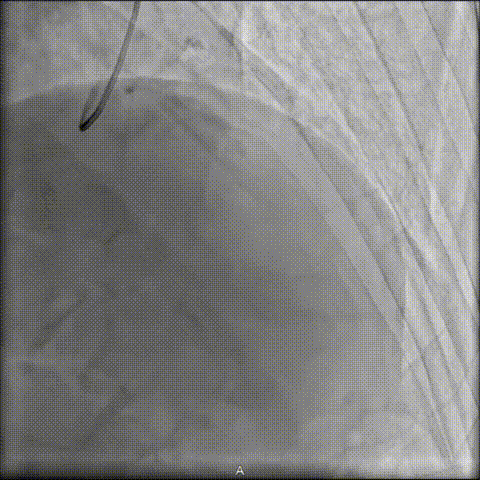

1 NC球囊预扩张失败

首先,采用2.5×15mm NC球囊以16atm×15s预扩张,病变处出现明显“腰征”,提示扩张不充分。